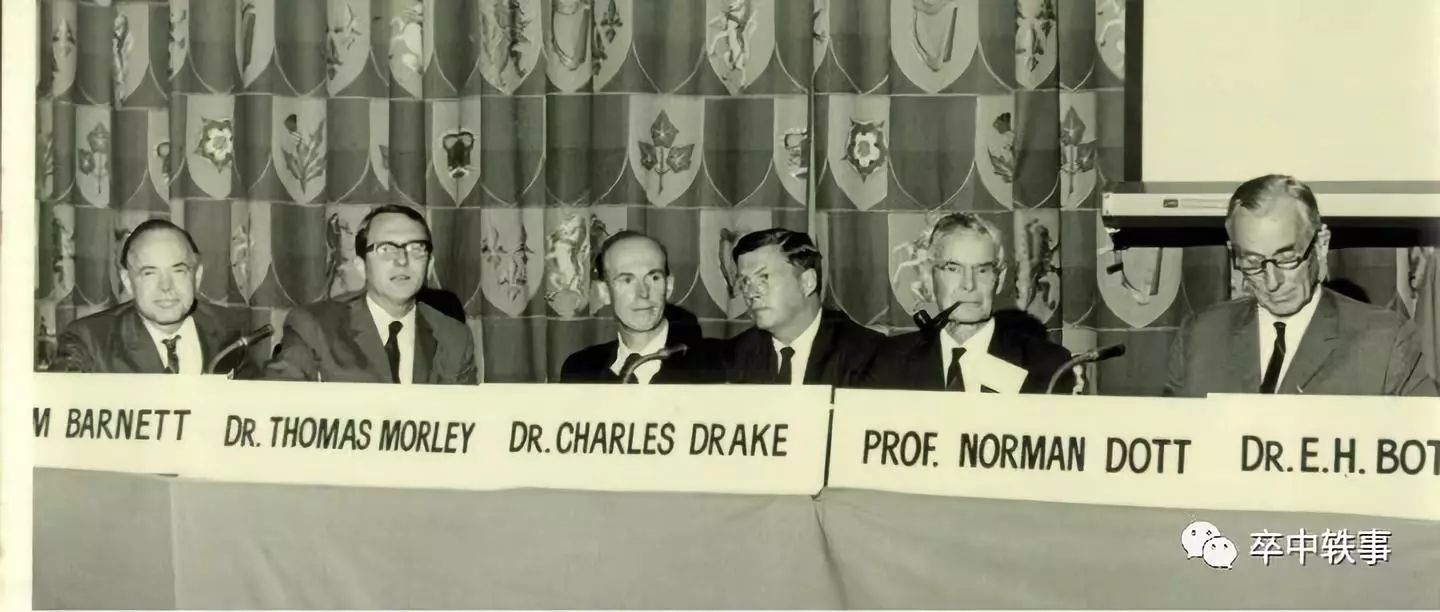

在1951年 McKenzie 推荐 Drake 从美国的神经外科之父 Harvey Cushing(1869-1939,见 Cushing 一章)那里获得 Routledge 访问学者奖学金,一家人去了英国。因为奖学金太少(Cushing 只允许 Drake 一人去),他们只好与 Kay 和 Henry Barnett(1922-2016,见 Barnett 一章)分租一套住房,两家人因此成为一生的好朋友。

Drake 在伦敦的皇后广场医院进修神内,同时观察欧洲神经外科大师们的手术,包括第一个开颅 “观察和包裹” 脑动脉瘤的 Norman Dott(1897-1973)。在牛津 Drake 结识了 Hugh Cairns(1896-1952),在斯德哥尔摩他结识了 Herbert Olivecrona(1891-1980,在1932年第一个切除小脑动-静脉畸形),在巴黎他结识了 Gerard Guiot(1912-1998)。